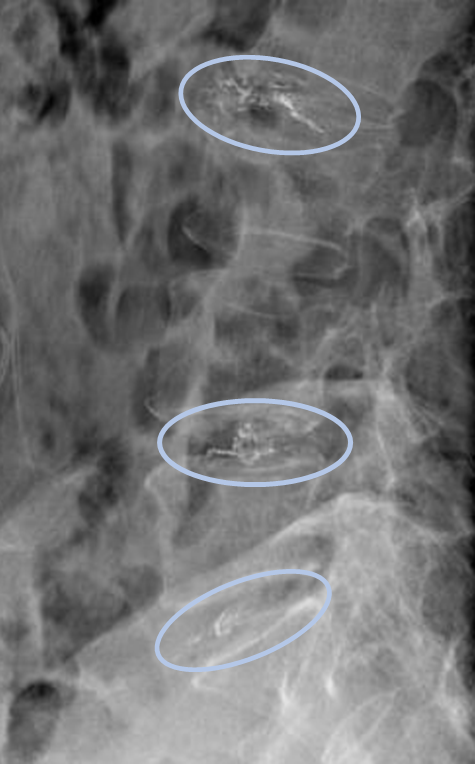

DiscoGelを入れた後の画像になります。